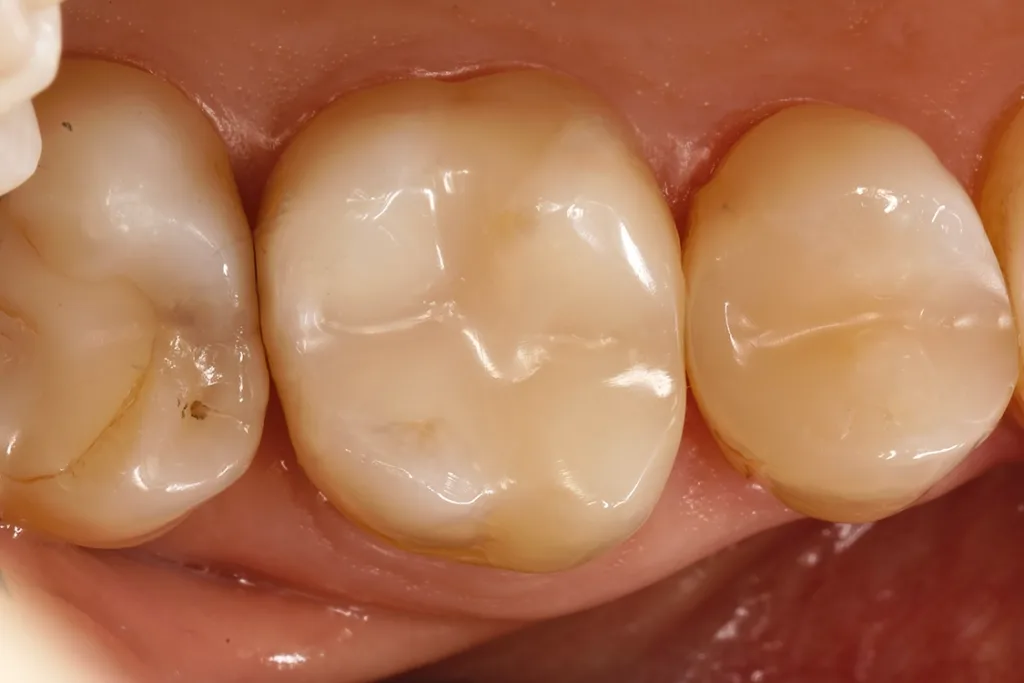

Die Patientin erhielt einen Kostenvoranschlag über Mehrkosten-Kompositrestaurationen und zusätzlich eine Honorarvereinbarung auf den Steigerungsfaktor 5,0. Dieser lag in der Vorhersehbarkeit des überdurchschnittlich hohen Schwierigkeitsgrades und Zeitaufwandes begründet, da die Okklusion sehr feinfühlig und eventuell in mehreren Folgesitzungen feinadjustiert werden muss. In dem Zahn 37 befand sich eine ältere, insuffiziente Amalgamfüllung, die klinisch eindeutig eine Austauschindikation aufwies. Die Abbildung 1 zeigt die unter FACE-Light [17] vollständig exkavierten, mit Kofferdam isolierten Kavitäten an den Zähnen 37 und 36. Aufgrund der Freiendsituation des distalen Kavitätenanteils des Zahnes blieb zur Formung nur eine zirkuläre, anatomisch geformte Tofflemire-Matrize 1001 C (Kerr Hawe SA, Bioggio, Schweiz). Die adhäsive Versorgung beider Kavitäten erfolgte über ein Zwei-Schritt-Universaladhäsiv (G2-BOND Universal, GC Corp., Tokyo, Japan [16,20,101,104,112,113]).

C-P ErnstAls Restaurationskomposit kam erstmals das „trocken“ zu werden, eine kaum vorhandene Klebrigkeit am Instrument und eine hervorragende Adaptation an den Kavitätenwänden. Am Zahn 36 erfolgte der Aufbau durch die Modellation einer einzigen, horizontal aufgebrachten Portion Komposit. Auf eine farbliche Charakterisierung der Fissuren wurde bewusst verzichtet: Neben dem doch sehr seltenen, diesbezüglich vorhandenen Patientenwunsch zeigt sich doch eine potenzielle Gefahrenstelle gerade bei dunklen Malfarben. Das Polymerisationslicht durchdringt diese nicht so gut, was wiederum zu einer ungünstigeren Aushärtung und in Folge zu einer reduzierten kohäsiven Stabilität der Gesamtrestauration führen kann. Die Publikation von Pucci et al. [86] zeigte eine Bruchfestigkeit von lediglich 11 und 10 MPa bei einer braunen bzw. schwarzen Malfarbe – bei 29 MPa in der Kontrollgruppe und 20 bzw. 24 MPa bei zwei weißen Malfarben. Die Abbildung 2 verdeutlicht das Ergebnis bei einer weiteren Adjustierung der Kaufläche nach einer Woche.